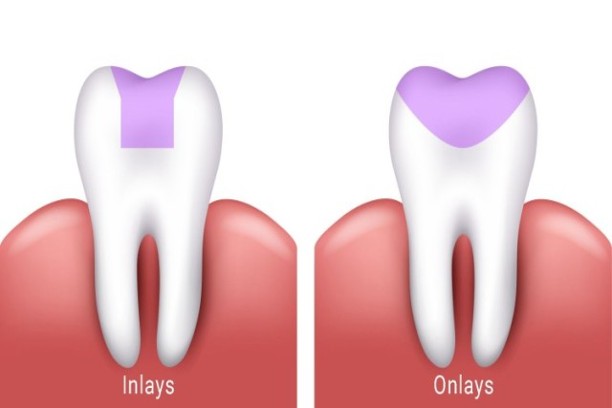

Inlays and Onlays

Precise restorations for moderately damaged teeth without full crowns.